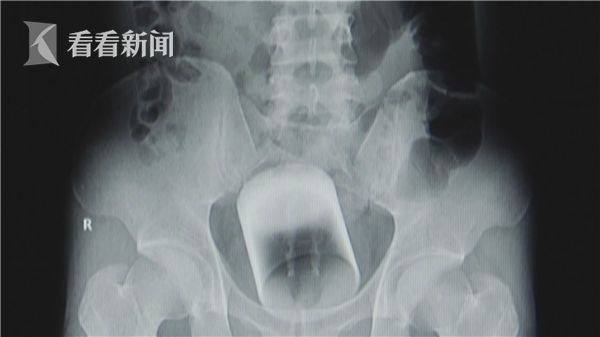

“患者腹部X光结果可以很清晰地看到盆腔正中有一个倒着的略微倾斜的圆柱形致密影,位于直肠中上段。”据接诊小张的结直肠肛门外科二区蔡永华主治医师介绍说,该异物距离肛门有近7厘米远,检查发现周围直肠黏膜正常,无水肿、出血等。